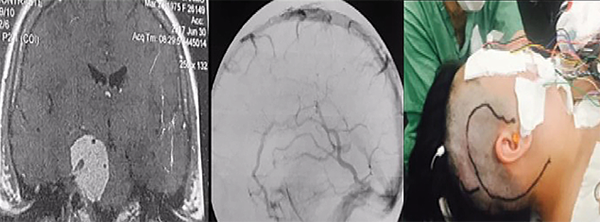

La resonancia magnética muestra la extensión y la relación de la lesión con el tronco encefálico, vasos y pares craneales, demostrando claramente cuando se produce el desplazamiento y la compresión de las estructuras normales. La resonancia magnética con gandolinio a menudo demuestra una lesión con realce intenso y homogéneo. En T1 el tumor tiene un aspecto isointenso, mientras que en TR largo (T2 y Flair) es hiperintenso. Además, es bastante hidratado y tiene una superficie externa ligeramente lobulada. La confirmación de edema en T2 en el tronco encefálico caracteriza la invasión de la aracnoides y generalmente es un signo de mal pronóstico cuando se trata de resecar el tumor por completo.3,4 La resonancia magnética de alta definición es esencial para la planificación quirúrgica. La vascularización del tumor y su relación con los vasos importantes se pueden demostrar mediante angiorresonancia magnética, angio-tomografía computarizada tridimensional multicorte o mediante arteriografía digital. Es importante estudiar el suministro vascular y los desplazamientos, estenosis u oclusiones de las arterias basilar, carótida interna y sus ramas. Incluso en los casos en que la arteria basilar está involucrada por el tumor hay un buen plano de clivaje con éste. Estos tumores generalmente son irrigados por ramas de la arteria carótida externa y por ramas del tronco meningohipofisiario (arteria de Bernasconi- Cassinari) generalmente aumentado.20,21 Los tumores hipervascularizados se pueden embolizar en el período preoperatorio reciente, pero generalmente la coagulación de la base del tumor al comienzo de la cirugía es suficiente para prevenir un sangrado mayor. La ubicación del drenaje de la vena de Labbé es crucial cuando se pretenden llevar a cabo abordajes en los que sea necesaria la retracción del lóbulo temporal, como un abordaje petroso (Figura 3). Su visualización preoperatoria se puede obtener mediante angio-tomografía computarizada - venografía o angiografía de fase venosa. Este conocimiento preoperatorio es muy importante para planificar el abordaje quirúrgico a fin de preservar la vena de Labbé y prevenir complicaciones venosas.22

Los abordajes petrosos son pre-sigmoideo retrolaberíntico, pre-sigmoideo translaberíntico y petrosectomía total. Estos abordajes se utilizan cuando la lesión se encuentra en la fosa media, fosa posterior y la región clivus (Figuras 3 y 4). Si el paciente tiene buena audición previa, se prefiere el acceso pre-sigmoideo retrolaberíntico. Cuando no hay audición preservada es posible extirpar los canales semicirculares, y este abordaje se denomina pre-sigmoideo translaberíntico. Para los tumores gigantes que cruzan la línea media en la región prepontina es necesario un abordaje más lateral y extenso, a través de la petrosectomía total (petrosectomía posterior asociada con la petrosectomía anterior). La cirugía se realiza con el paciente en posición decúbito dorsal, con la cabeza vuelta hacia el lado opuesto. La incisión en la piel se realiza en forma semicircular a partir la región temporal, cuatro centímetros por encima del arco cigomático, pasando tres centímetros detrás de la oreja, extendiéndose dos centímetros detrás de la punta del mastoides. Para evitar fístula del LCR postoperatoria, se utiliza la reconstrucción de la base del cráneo con la fascia temporal, que se diseca con el periostio mastoideo, la fascia craneocervical y el músculo esternocleidomastoideo, que se separa de su inserción, formando un gran colgajo vascularizado que es girado para atrás al final de la cirugía para cubrir todo el campo quirúrgico. La corteza mastoidea es drenada, identificándose el laberinto y el canal del nervio facial. Estos canales no son abiertos. Se realizan dos trepanaciones por encima y dos por debajo del seno sigmoideo y, con una broca de alta rotación, se realiza una craneotomía, exponiendo las fosas media y posterior (retrosigmoide). Los senos petroso superior, sigmoideo y transverso son expuestos. Las celdas mastoideas retrofaciales se eliminan hasta el bulbo yugular. La duramadre anterior es expuesta al seno sigmoideo. Se extraen las células cigomáticas y supralaberínticas, manteniendo intactos los canales semicirculares y el oído medio. El seno petroso superior se secciona anterior a su entrada en el seno sigmoideo. Antes de esta maniobra, debe conectarse con un punto o con microclips. Luego, se realiza una incisión en el tentorio, inicialmente perpendicular al seno petroso superior de dos a tres centímetros y luego medialmente, paralelo al seno transverso en otros tres centímetros. Esta maniobra permite una amplia exposición del cerebelo, separándolo a partir del aspecto posterior del lóbulo temporal en "libro abierto". Se debe tener cuidado para preservar la vena de Labbé, que tiene una anatomía variable y generalmente ingresa al seno transverso diez milímetros antes de su unión con el seno sigmoideo. La evaluación preoperatoria de la anatomía venosa es esencial para planificar este abordaje. La incisión del tentorio se continúa hasta la incisión donde se expone y preserva el IV par craneal. Algunas pequeñas venas puente basales en la base anterior del lóbulo temporal se coagulan y cortan, permitiendo una amplia exposición subtemporal. Se debe evitar la colocación de espátulas fijas con Leyla apoyando el lóbulo temporal y el cerebelo. En general, la espatulación leve realizada por el auxiliar de manera no continua es suficiente para exponer toda la región petroclival de los pares craneales III a VII y VIII. El nervio trigémino generalmente se puede ver desplazado posterior y superiormente. El tumor se desvasculariza por la coagulación bipolar de su inserción dural. Posteriormente, la resección intracapsular fragmentada del tumor se realiza con un aspirador ultrasónico, realizando una citorreducción del tumor, que permite la disección de la cápsula tumoral de los nervios, la arteria basilar y las arterias cerebelosa superior y cerebral posterior. El nervio abducente es muy delgado y frágil. El canal de Dorello se encuentra medial a los pares craneales VII y VIII, y esta región debe abordarse solo después de una resección extensa del tumor. Las extensiones tumorales de la parte posterior del seno cavernoso se resecan después del nervio trigémino. Toda infiltración del hueso petroso y el clivus se elimina con una broca de diamante. Después de la extracción total, la duramadre se cierra herméticamente o con un injerto de fascia y pegamento de fibrina. El abordaje presigmoideo translaberíntico es similar, pero con la eliminación adicional del laberinto al drenar los canales semicirculares, lo que agregará una exposición de aproximadamente 1,5 centímetros de cirugía y permitirá una mejor vista de las estructuras de la línea media. Esta apertura de los canales semicirculares causa sordera y sólo está indicada para pacientes sin audición viable previa.1

Figura 3:Resonancia magnética con gadolinio, corte coronal, que muestra un componente tumoral en la fosa posterior y en la fosa media. Caso ideal para el abordaje petroso (izquierda). Angiografía de fase venosa que muestra drenaje de la vena de Labbé en la unión del sigmoide con el transverso, sin contraindicar el abordaje petroso (centro). Incisión del abordaje petroso (también conocido como abordaje presigmoideo (supra/infratentorial) utilizado en este caso (derecha).